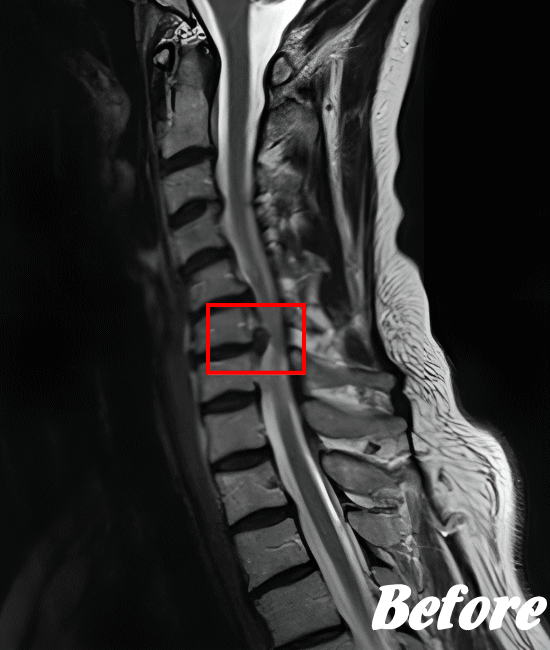

姿勢の悪さなどにより頚椎に負荷がかかり、椎間板を圧迫することで、線維輪が破れ、髄核が外側に飛び出し、炎症が発生します。また、飛び出た髄核が首の神経や血管を圧迫し、痛みや痺れなどの症状が現れます。これが『頚椎椎間板ヘルニア』です。

頚椎椎間板ヘルニアの多くは、首のクッションの役割をしている椎間板が圧迫を受け、その中にある髄核が飛び出し、神経根を刺激するからです。

頚椎を斜め後方へ反らせると上肢に放散痛が現れたり、首の可動域、感覚異常があるかどうか…等々を確認した上で、レントゲンやCT、MRIなどによる画像検査を行います。

HALOカイロプラクティック☆平和島整体院では、骨盤から背骨全体を調整し、首(頚椎)の詰まりを一つ一つ広げ、肩甲骨の可動を柔軟にし、首周りの筋肉をゆるめることで、首の負担が解消され、痛みや痺れを改善していきます。